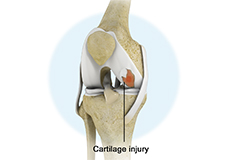

Articular Cartilage Injury

Articular or hyaline cartilage is the tissue lining the surface of the two bones in the knee joint. Cartilage helps the bones move smoothly against each other and can withstand the weight of the body during activities such as running and jumping.

Chondral or Articular Cartilage Defects

The articular or hyaline cartilage is the tissue lining the surface of the two bones in the knee joint. Cartilage helps the bones move smoothly against each other and can withstand the weight of your body during activities such as running and jumping.